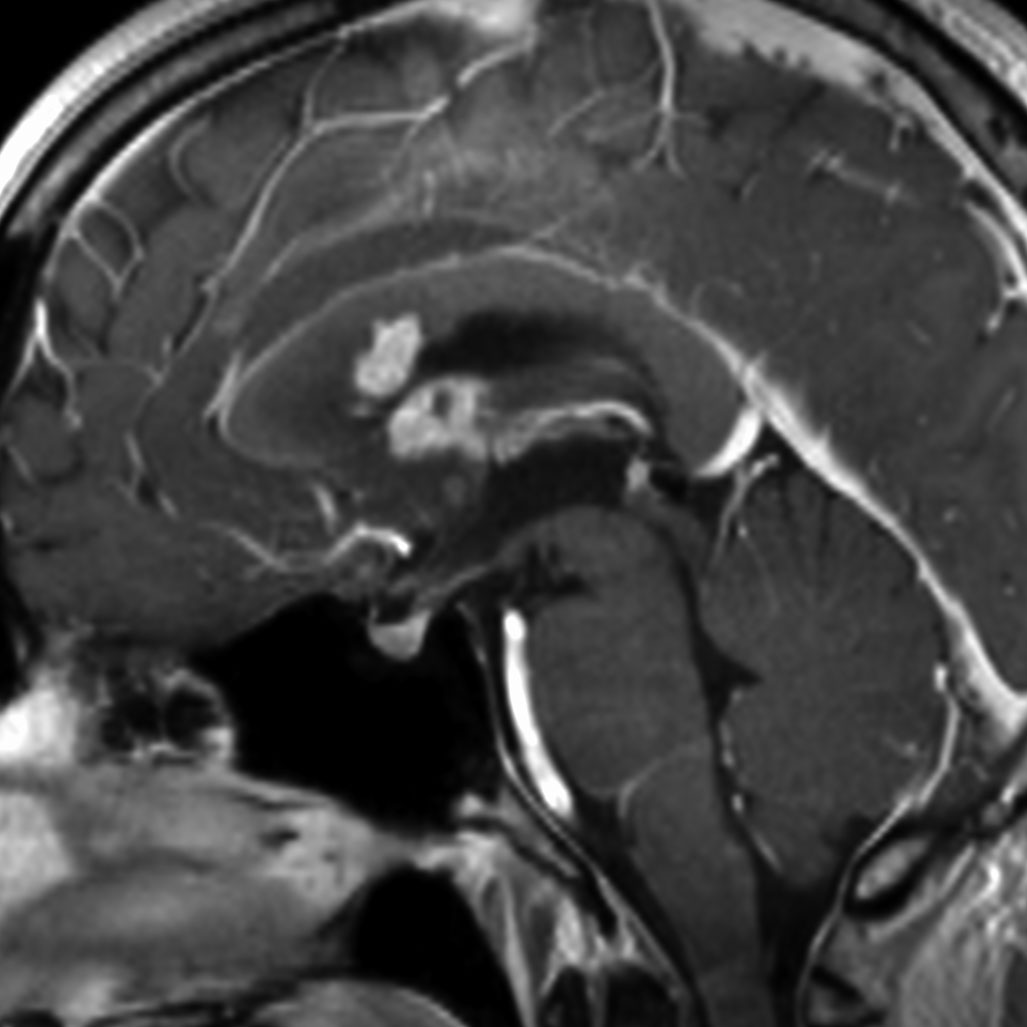

21歳男性で交通事故で偶然発見された両側前頭葉腫瘍です。

ガドリニウム増強では,前頭葉腫瘍というより,側脳室壁にベトベトくっついているような腫瘍です。germinoma特有のsubependymal infiltration像を示します。

生検後2ヶ月,セカンドオピニオンのために受診された時の画像です。腫瘍が縮小傾向にあります。入院中に行われた何度かのCT被曝の影響で,germinomaの退縮が生じたのだと判断しました。

左はICE化学療法 (IFO/CDDP/VP-16)前,右は1コース終了後です。腫瘍は顕著に縮小してgerminomaとして普通の化学療法反応性を示します。また,松果体と下垂体には腫瘍はありません。